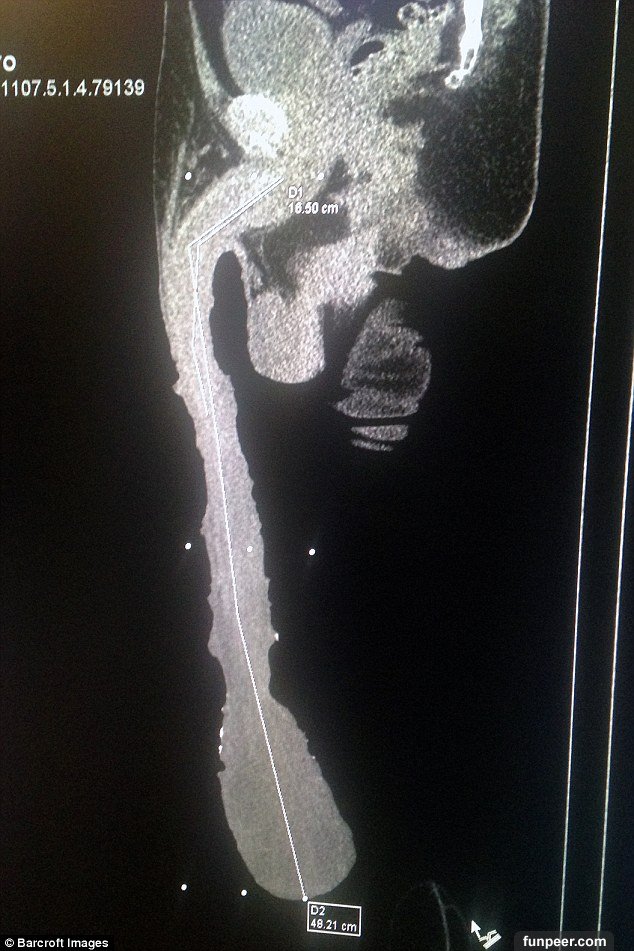

隨著「秤重GG」的影片在網路上爆紅後,許多人都質疑他胯下的那條巨根到底是真是假!所以他為了證明自己的清白,特地到醫院做檢查,並拍攝X光片證明全身上下都是「真材實料」...

不過醫生看完X光片表示,其實他那支長達48cm的大GG,其實有很大一部分都是包皮,其真實的長度可能只有7英吋(18cm),而且最後來建議他如過未來有想要愛愛或是生小孩的打算,就一定要做「縮小手術」,否則一輩子都要保持處子之身....